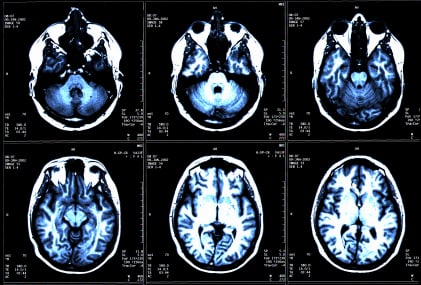

Quando si parla di CCVSI ci si riferisce a un difetto del flusso del sangue. In particolare di malformazioni che causano il restringimento delle principali vene cerebrali e che di fatto impediscono il corretto flusso di sangue a livello del collo, del torace e della colonna vertebrale. Questo restringimento, secondo Zamboni, sembrerebbe correlato alla sclerosi multipla. Dunque la correzione della CCVSI attraverso un intervento di chirurgia endovascolare (angioplastica), potrebbe essere un efficace trattamento per migliorare i sintomi della malattia.